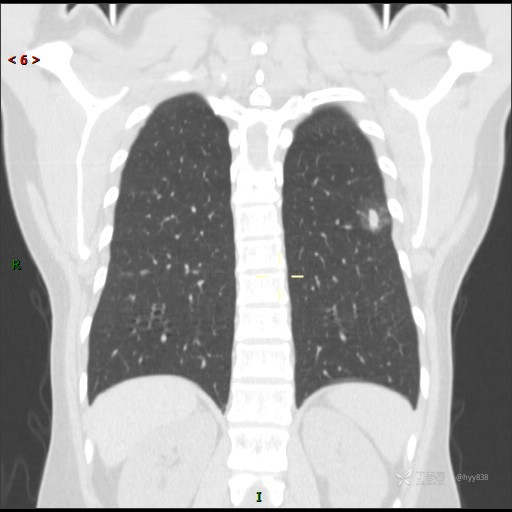

胸膜下“煎鸡蛋征”,感染 VS 炎症 VS 肿瘤,挑战有你---结果公布~

患者性别:女

患者年龄:46岁

简要病史:干咳半月伴左胸部不适

辅助检查:CT

临床诊断:结节

讨论:病变性质?